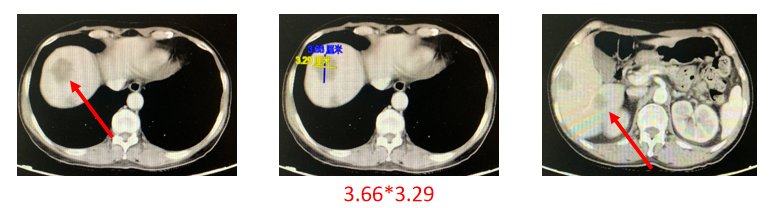

2019年8月19日CT:

2019年10月22日CT:

2019年12月4日CT:

2020年2月18日CT: